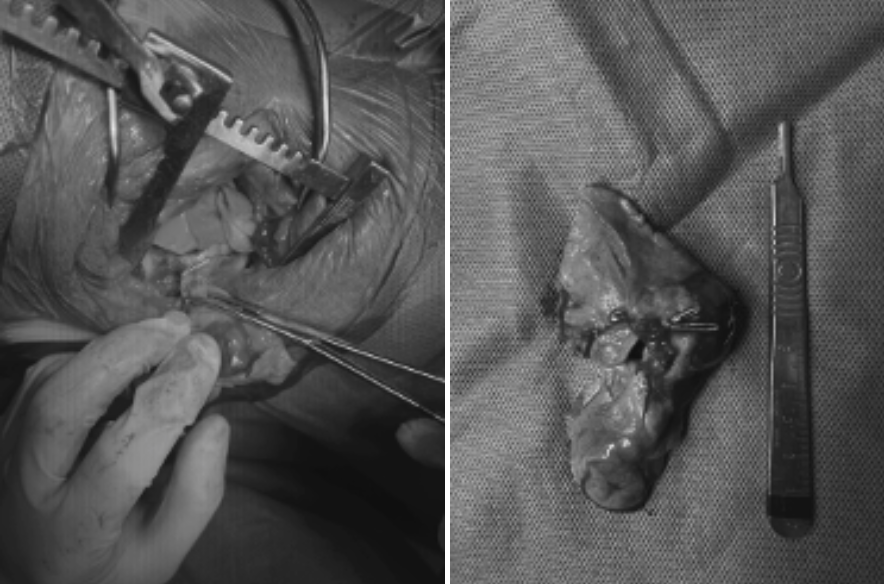

02 강아지 폐종양 수술 및 회복과정

시츄 강아지 환자는 좌측 전엽 절제술(lobectomy)을 진행했습니다. 마취 중 특이사항은 없었으며, 수술 후에도 안정적으로 회복하였습니다. 퇴원 시에는 활력과 식욕이 회복된 상태로, 호흡 상태 역시 안정적이었습니다.

울산 강아지 폐종양 수술 / 출처: 에스동물메디컬센터